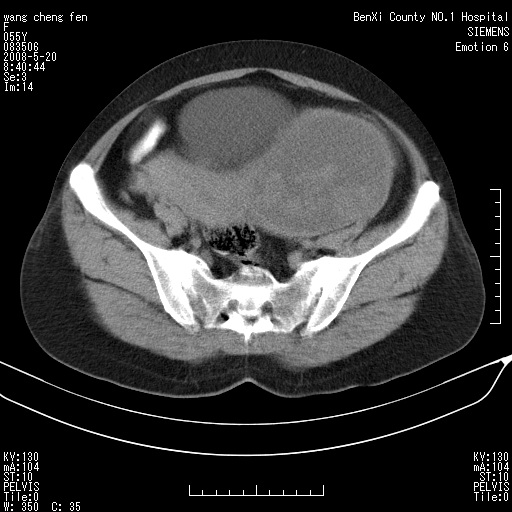

女、绝经后阴道流血3个月

左侧附件区可见一囊性占位,边缘清楚,内可见不规则形软组织影 ce:囊壁及内部可见强化 考虑 卵巢囊腺瘤

左侧附件区巨大囊实性病灶,边缘光整,病灶囊壁较厚,增强示囊壁及实性部分明显强化,强化呈度与宫体实质大致相同,宫腔积液征像,未见盆腔积液等其他异常,考虑左侧卵巢囊腺癌,不除外囊腺瘤及浆膜下肌瘤坏死

左侧附件区巨大囊实性病灶,边缘光整,病灶囊壁较厚,增强示囊壁及实性部分明显强化,强化呈度与宫体实质大致相同,宫腔积液征像,未见盆腔积液等其他异常。绝经后阴道流血3个月,结合病史左侧卵巢囊腺癌首先考虑,宫腔扩大不除外累及。期待结果。

支持浆膜下子宫肌瘤.之前由于网络原因未看全图片,现在重看,宫颈见一类圆形低密度影,增强轻度强化,低于肌层强化,宫腔扩大,考虑宫颈癌伴宫腔积液可能性大.